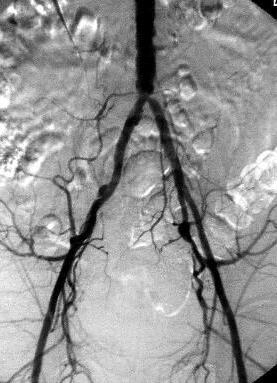

the pathological image-left and the physiological image-right

Adult man, 53-years-old,

admitted with pain in the legs - especially the left leg. Physical

examination reveals gangrene at the left foot

Atherosclerosis

is the main cause of peripheral vasclar diseases. Clinically they present

with intermittent claudication, pain at rest and gangrene.

D:

Peripheral vasclar

disease caused by atherosclerosis.